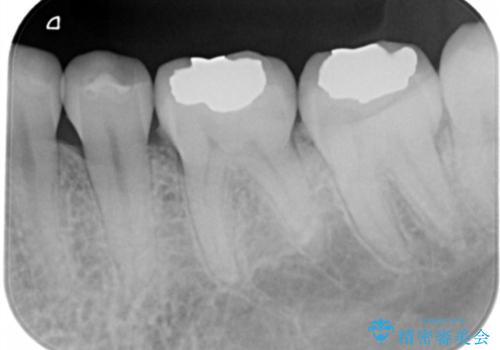

- 左下奥歯のメタルインレーを白くしたいと希望された患者様です。

形態、切削量などを考慮し、セラミックインレーにて治療を行いました。

メタルインレー、う蝕除去後にCRにて裏層した上で、形成・印象を行いました。